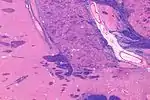

The substantia innominata also innominate substance, or substantia innominata of Meynert (Latin for unnamed substance) is a series of layers in the human brain consisting partly of gray and partly of white matter, which lies below the anterior part of the thalamus and lentiform nucleus. It is included as part of the anterior perforated substance (as it appears to be perforated by many holes which are actually blood vessels). It is part of the basal forebrain structures and includes the nucleus basalis. A portion of the substantia innominata, below the globus pallidus is considered as part of the extended amygdala.[1]